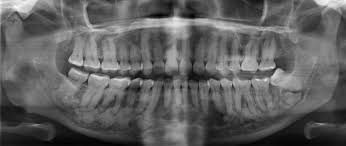

Periapical cemental dysplasia is a benign condition mostly seen in patients over 20 years of age and is more common in women. The lesion occurs in and near the periodontal ligament around the apex of a tooth, usually a mandibular incisior. Most cases usually present with multiple lesions involving the apices of several mandibular anterior teeth or bicuspids. Since the lesion is asymptomatic, it is often accidentally discovered during routine intraoral roentgenographic examination. In the early stage of development, the lesion appears as a periapical radiolucency resembling periapical granuloma or cyst. The second stage in the development of the lesion is the beginning of calcification in the radiolucent area. The third stage appears on the roentgenogram as a well-defined radiopacity that is usually bordered by a thin radiolucent line. No treatment is required, as it is harmless, and only periodic observation is required. It is difficult to radiographically distinguish this lesion from a periapical granuloma. Hence to make this distinction, vitality testing of the pulp should be done. No treatment is required for this condition.